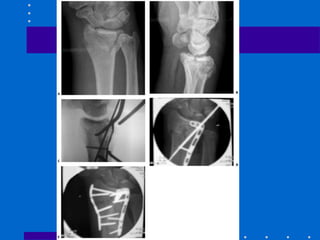

A,B Tração não reduziu córtex palmar C,D Placa

placa de coluna radial utilizada( pode ser Fio K)

A,B Tração nãoreduziu córtex palmar C,D Placa volar com cominuição estilóide radial residual E,F placa de coluna radial utilizada( pode ser Fio K)